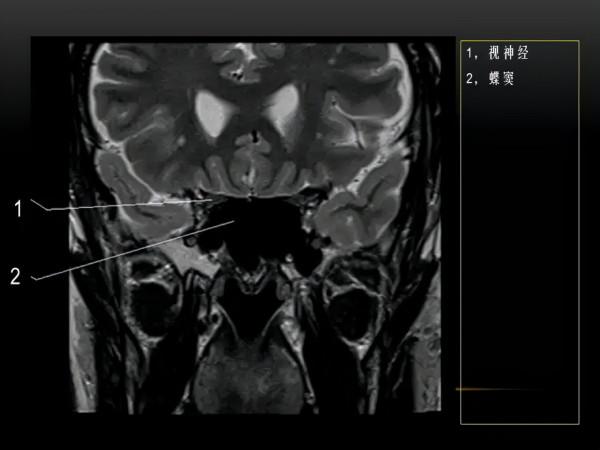

MRI下眼部及鼻竇的冠狀位解剖